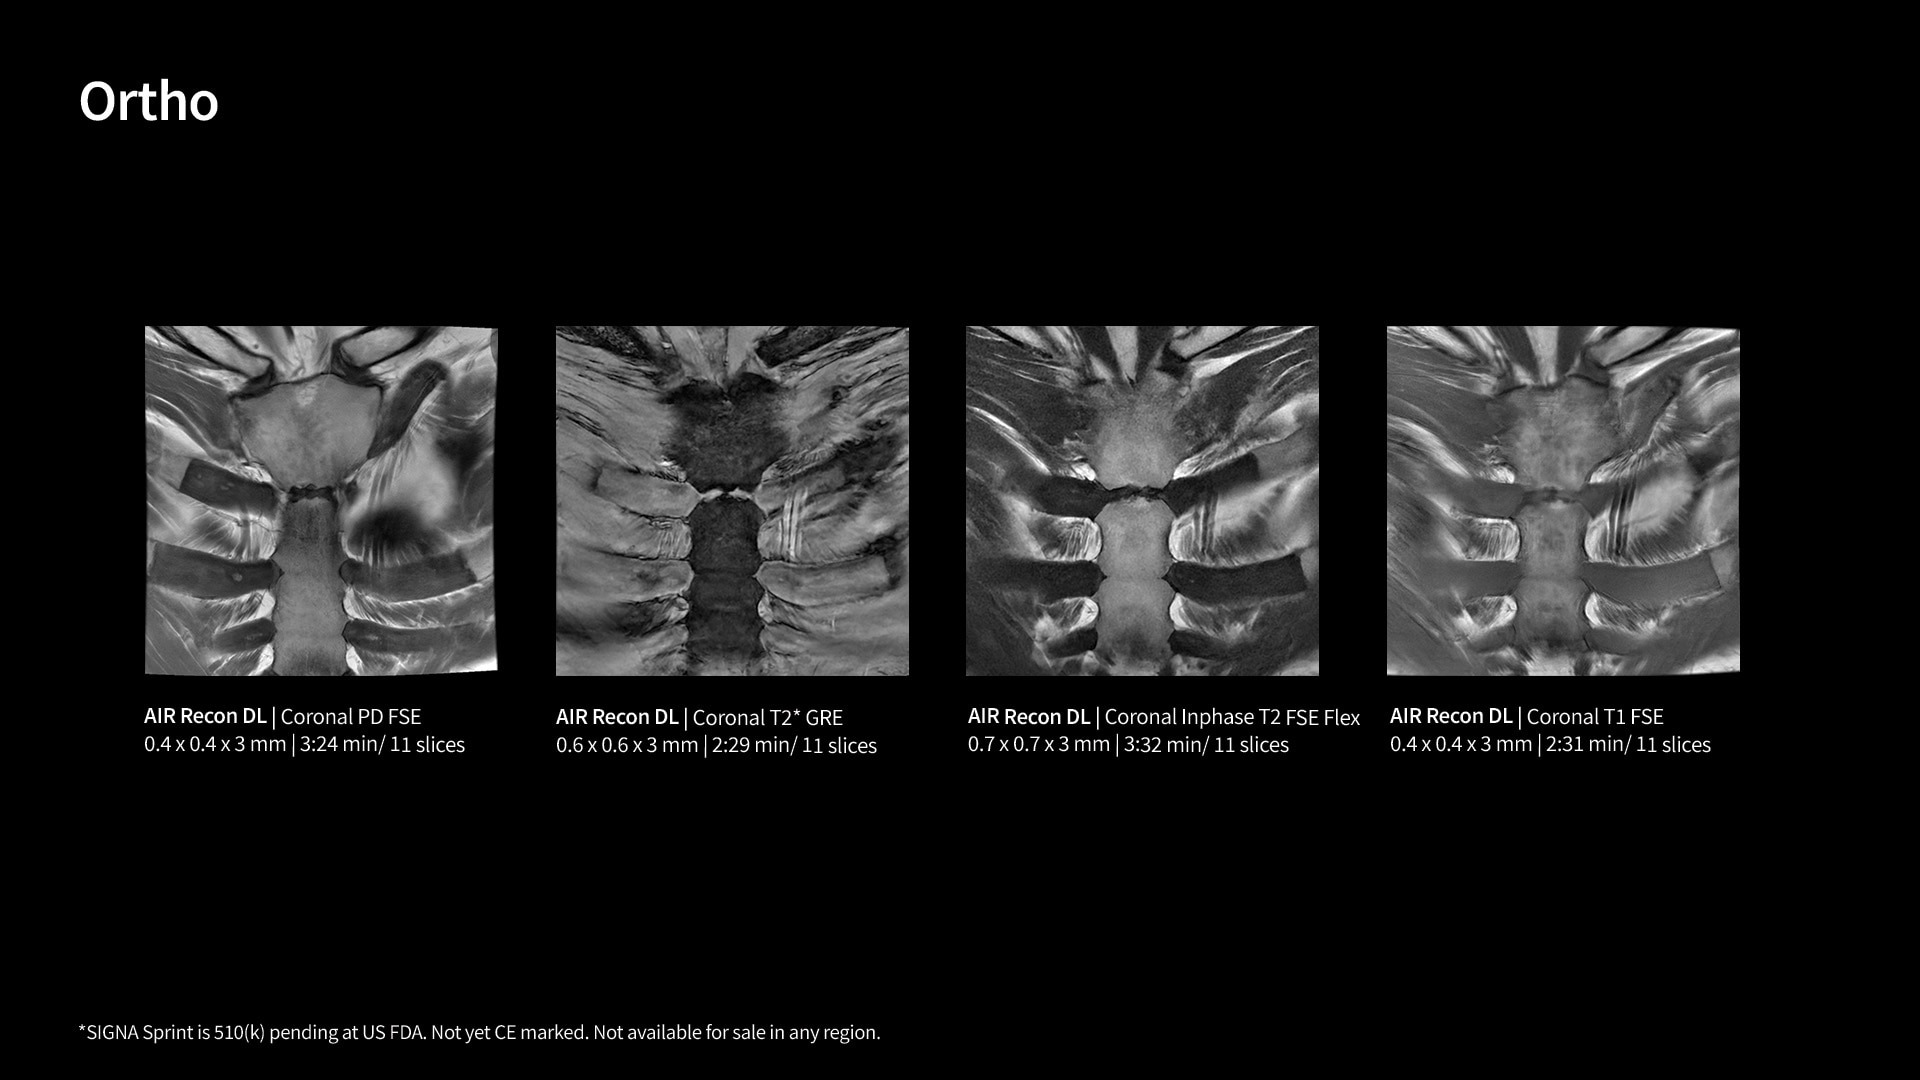

A deep-learning-based reconstruction algorithm that enables sharper, clearer images with better SNR without compromising scan time.